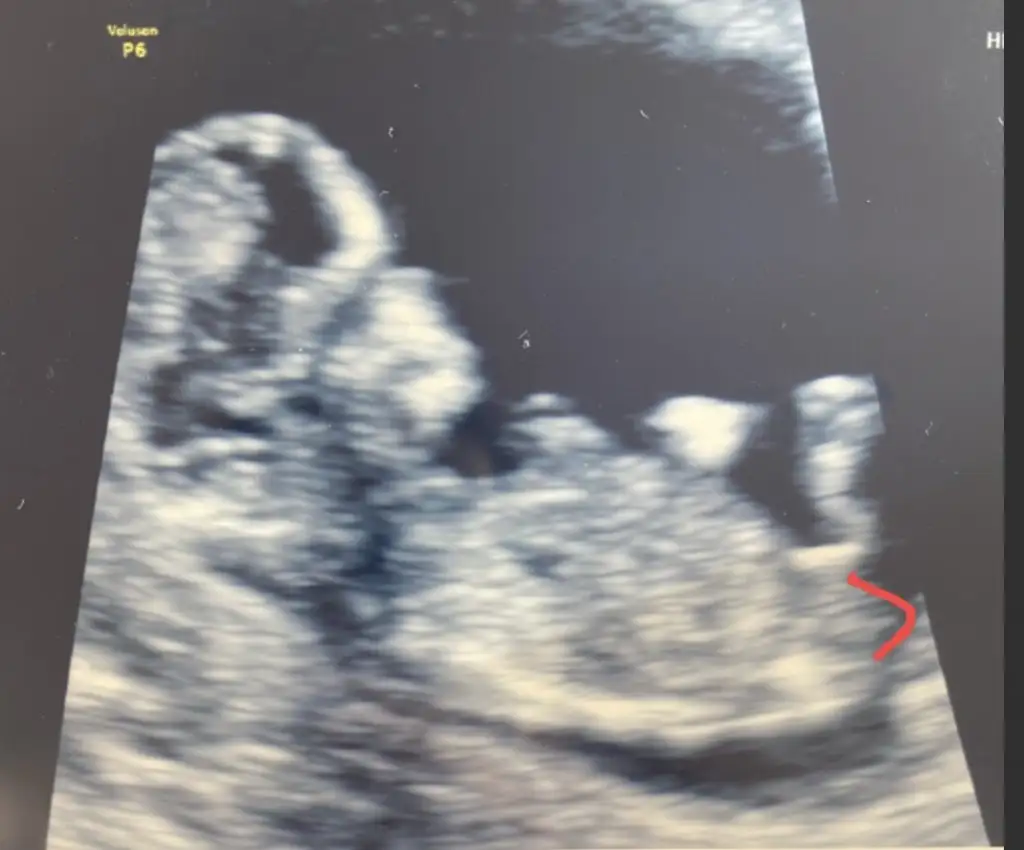

Sağlıkla gelsin prensesTahmin doğruydu canım 12 usg kız dedin 14 haftamda dr kıza benziyor dedi.. Sonradan kız olduğu kesinleşti :) teşekkür ederim

kız mı bu minnoşIkra meyra ve mesajımı okuyan diğer kızlar,rica etsem bir tahminde bulunur musunuz :)

Ben de çok kız hissediyorum ama doktorumuz erkek dedi ,bir de sizin tahminlerinizi almak istedim :) siz benzettiniz mi?kız mı bu minnoş

Erkek görünüyorIkra meyra ve mesajımı okuyan diğer kızlar,rica etsem bir tahminde bulunur musunuz :)